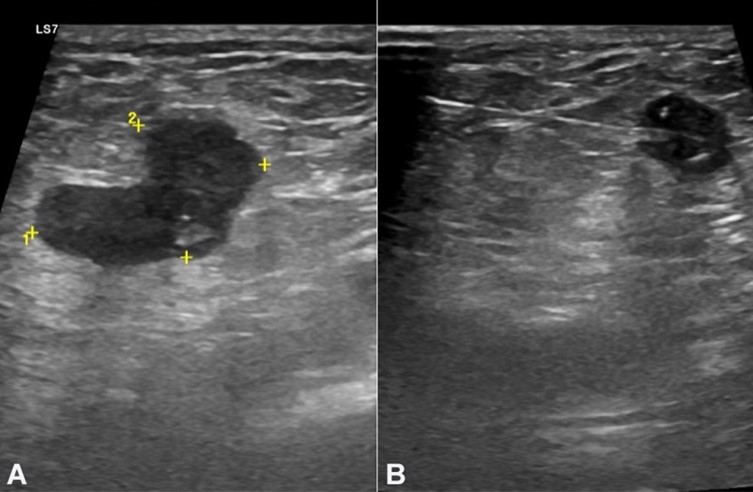

A 71-year-old woman with a history of total hysterectomy and bilateral salpingo-oophorectomy by adenomyosis with benign final pathology, 20 years ago, came to the Emergency Department for abdominal pain in the lower quadrants, of sudden onset, associated with anorexia and nausea over the last 36 hours. On the physical examination, she had hemodynamic stability, apyrexia, and abdominal right lower quadrant pain without signs of peritoneal irritation. Analytically, she had increased inflammatory parameters, and ultrasound revealed uncomplicated acute appendicitis (Figure 1).

In the third year of follow-up, the patient presented a right inguinal swelling. The ultrasound depicted two suspicious lymph nodes (Figure 3). The tru‐cut biopsy revealed adenocarcinoma, with areas of extracellular mucin and an immunophenotypic profile compatible with primary colorectal neoplasia (Figure 4). At that time, tumor markers were elevated, the LDE did not identify endoluminal lesions, and CT did not show the involvement of others lymph nodes groups. The patient was re-staged to stage IV and proposed for palliative chemotherapy with FOLFIRI and bevacizumab. Five months later, due to abdominal complaints, the patient underwent an abdominal CT that identified liver metastasis and findings suggestive of peritoneal carcinomatosis. The patient died 3 months after by digestive bleeding and suspected gastrointestinal perforation due to bevacizumab toxicity and disease progression.